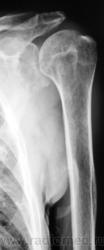

Пациент направлен хирургом на рентгенографию плечевого сустава. Травма, вроде-бы была. Хирург, не мудрствуя, направил пациента на рентгенографию. Пациент предъявляет жалобы на боли в области плечевого сустава, руку поднять не может. Врача-рентгенолога, на момент исследования в рентгеновском кабинете не было.

Вы совершенно правы Татьяна Валентиновна. Я намеренно "обрезал" снимок, произведенный лаборантами, дабы акцентировать внимание на латеральном угле лопатки. Суставная поверхность лопатки и шейка внушают серьёзные подозрения, и с учетом "пороза" и структуры.

Но, я неоднократно повторяю, что работаю с очень хорошими лаборантами, и они прекрасно понимают, да и убедились, что если написано - рентгенография голеностопного сустава, то зачастую "написанное" не есть "то, что надо". Так и в данном случае лаборанты "захватили побольше", и дай бог, им здоровья и всего самого наилучшего.

Снимок "без обрезания" - ниже. Врача-рентгенолога в кабинете не было, лаборанты, оценив его, начали "пытать" пациента. Оказалось, что флюорографию органов грудной полости, этот пациент, "проходил" лет 5 тому. Ну, и лаборанты приступили к стандартному исследованию органов грудной полости.